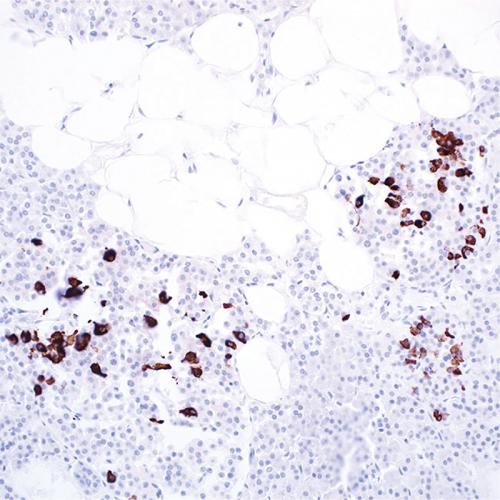

B細(xì)胞合成的免疫球蛋白是一個多聚體,它由2個重鏈和2個輕鏈(Lambda)組成。在不同階段或同一階段產(chǎn)生幾種不同類型的重鏈,但輕鏈都為同一型,即Kappa鏈。正常淋巴結(jié)中表達(dá)不同輕鏈的B細(xì)胞數(shù)κ∶λ約為2∶1。Lambda的表達(dá)受限提示單克隆增生和腫瘤形成。腫瘤性增生時呈限制性表達(dá),即只有一條輕鏈κ或λ表達(dá),相反如果檢測結(jié)果為κ和λ都看到表達(dá),則沒有限制性,為增生性病變。在B細(xì)胞淋巴瘤中,免疫球蛋白輕鏈κ和λ往往呈特異性限制性表達(dá),是B細(xì)胞單克隆性增生的標(biāo)志。因此在臨床上,測定 κ/λ 比值可用于區(qū)分腫瘤B細(xì)胞增殖和反應(yīng)性淋巴樣增生。

由于組織中富含免疫球蛋白,因此采用免疫組化技術(shù)檢測Lambda會伴隨大量背景染色的形成,這將影響染色結(jié)果判讀。而原位雜交探針具有高度特異性,在石蠟切片中容易涉透到組織中去與靶標(biāo)雜交,并且得到穩(wěn)定優(yōu)質(zhì)的染色結(jié)果。

Lambda鏈探針試劑,分別針對Lambda鏈mRNA序列特異設(shè)計靶點檢測,具有高度特異性和敏感性。通過多聚體酶標(biāo)技術(shù)-DAB顯色系統(tǒng),極大提高了檢測信號強(qiáng)度。

1、胞漿染色定位清晰,陽性信號對比度高。不存在交叉反應(yīng),避免了免疫組化檢測的高背景,染色結(jié)果可直接進(jìn)行判讀。